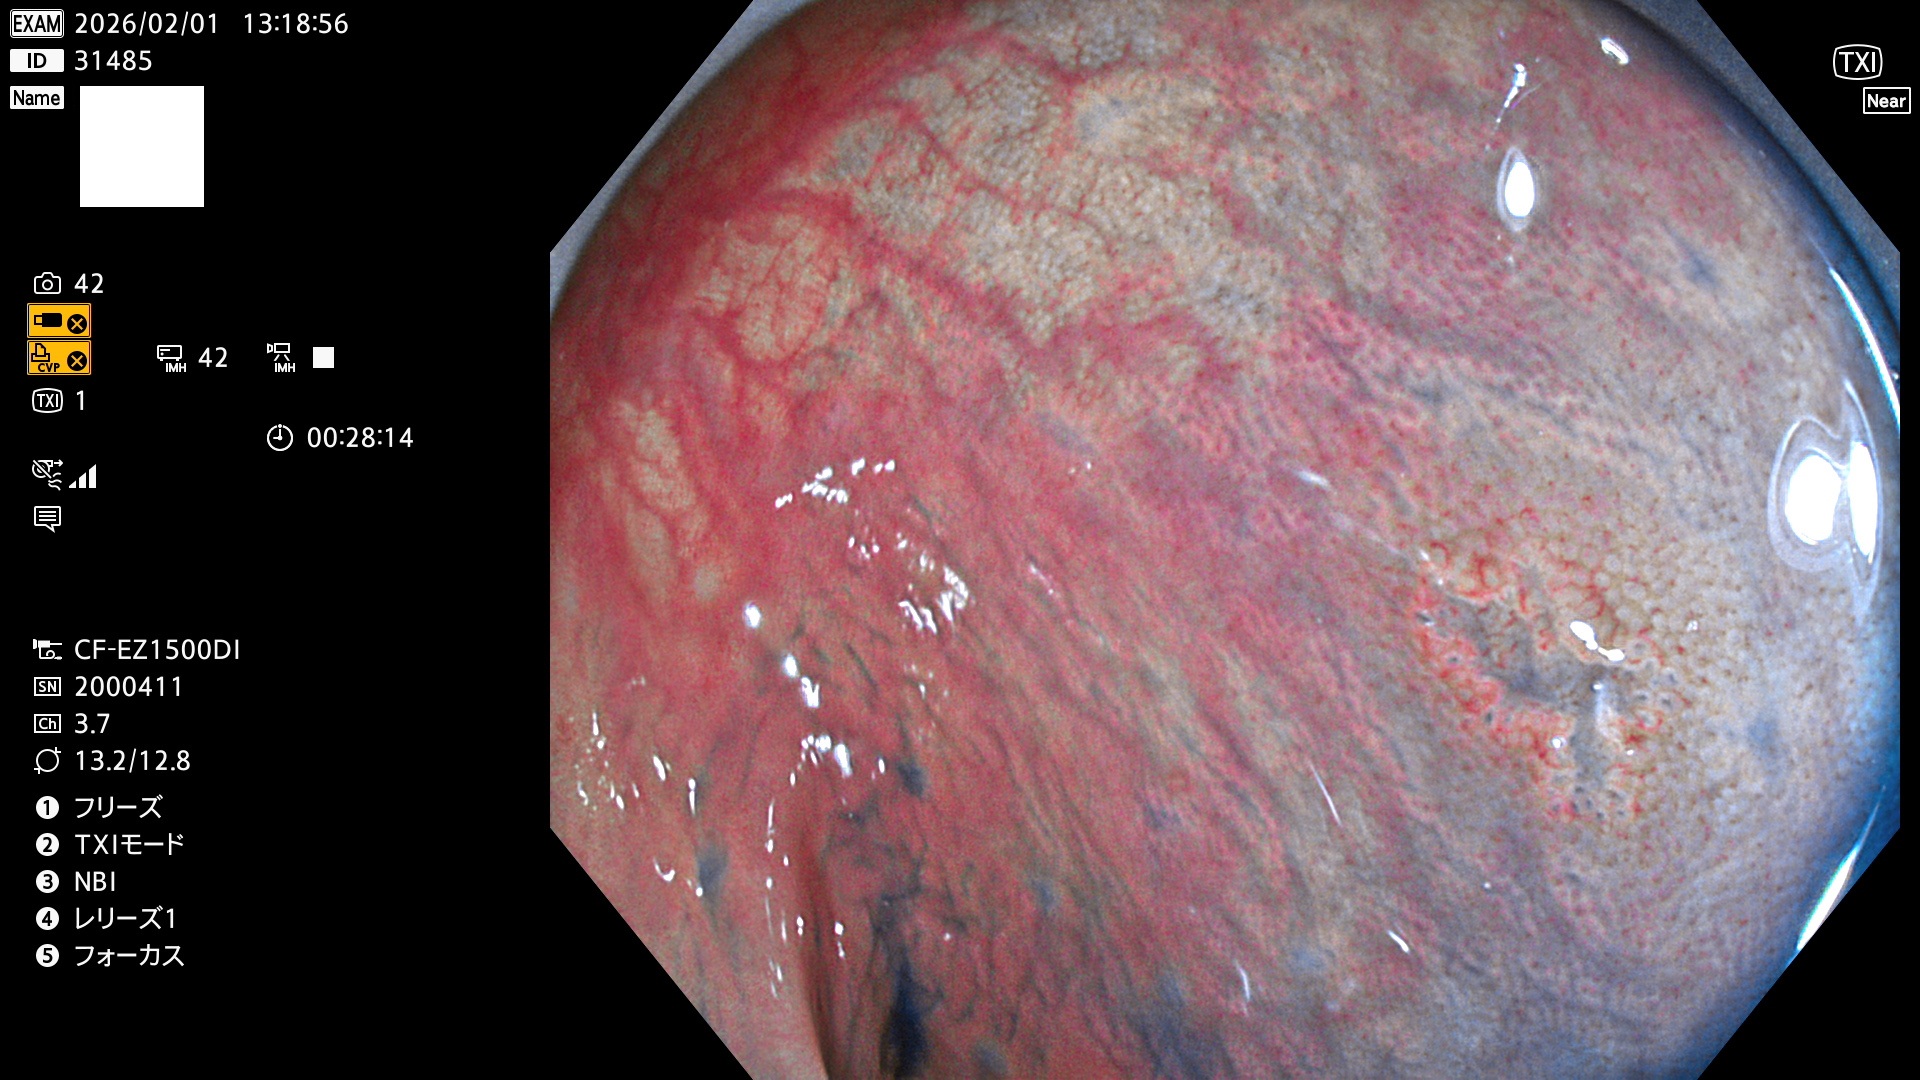

完全に平坦な物をUb、陥凹している物をUcと呼びます。Ubは認識が困難で、Ucはびらん(炎症)と紛らわしいために見落とされやすく、「内視鏡後・大腸癌」の原因になります。

毎週の検査(木・金・土・日)に発見されたUbとUc型・腺腫を、その週の日曜の夜にUPし1週間、提示します。

写真公開の目的は「透明性・信憑性の担保」ですが、公開を希望されない方はメールで御連絡下さい。直ちに削除いたします。

2026年1月29日〜2月1日の4日間(40件)10個 (Uc_ADR=10個/40人=25%)